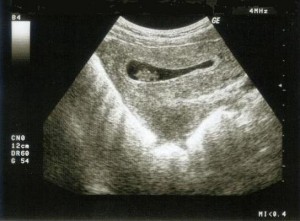

(IlMinuto) – Cagliari, 2 settembre – V.D., la donna serba di 28 anni, madre di quattro bambini di 8, 6, 5 e 3 anni e incinta di due gemelli, è ancora rinchiusa nel carcere di Buoncammino, a Cagliari. Lo rende noto Maria Grazia Caligaris, presidente dell’associazione Socialismo Diritti e Riforme. “Il magistrato di Latina – spiega Caligaris - ha ritenuto lo stato di gravidanza compatibile con la detenzione negando gli arresti domiciliari. Una decisione in contrasto con il senso di umanità”. “Nelle scorse settimane – precisa l’esponente socialista - la giovane è stata ricoverata nell’ospedale San Martino di Oristano per minaccia d’aborto”. Ora la donna sta meglio, ma – sottolinea Caligaris - “è in contrasto col senso di umanità un provvedimento che nega una condizione detentiva meno pesante a una persona che non ha ucciso, non ha trafficato droga, non ha picchiato o violentato qualcuno, né è associata a qualche gruppo mafioso”.